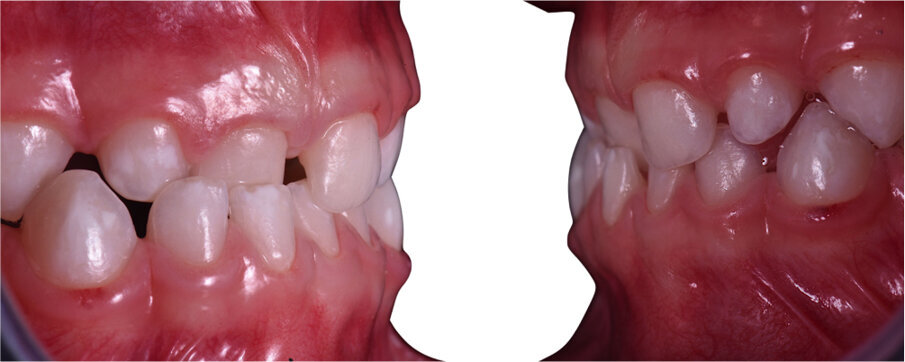

Caso 2 Paziente di anni 4, malocclusione dentale di III Classe, morso crociato monolaterale dx. La paziente viene trattata con dispositivo Amcop TC 2, il quale indossato tutte le notti e 1 ora di pomeriggio in 8 mesi risolve la malocclusione ripristinando il corretto rapporto occlusale; durante la terapia si riscontra un netto miglioramento della respirazione nasale e quindi il ripristino delle normali funzioni respiratorie. Il dispositivo, nei mesi successivi, viene indossato dalla paziente solo la notte per stabilizzare il caso e per guidare la crescita nel miglior modo possibile; all’età di 6 anni la paziente viene sottoposta a check-up ortodontico completo e quindi a panoramica e teleradiografia per poter analizzare anche la previsione di crescita e stabilire un eventuale step elastodontico (Figg. 15-23).